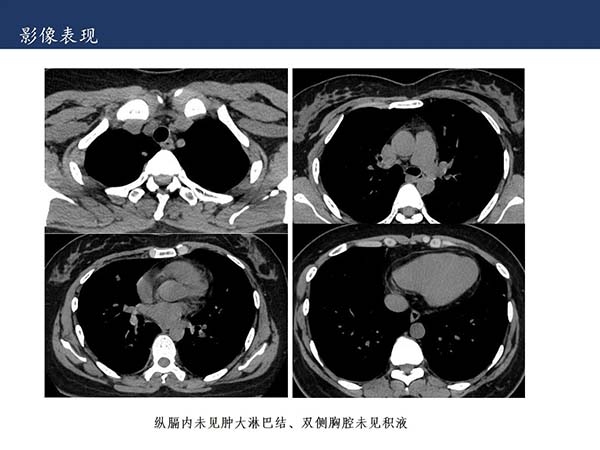

【杨柳科普】肺上皮样血管内皮瘤的影像表现